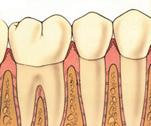

Sanatate parodontala

culoare roz coral

gingia este ferm atasata de dinte

lipsa sângerarii

aspect de "gravura punctata"